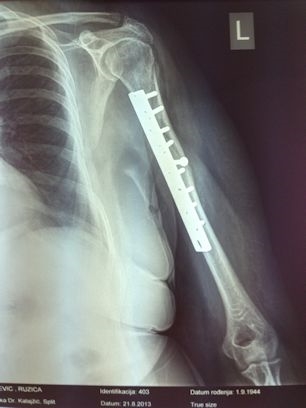

Koštani lomovi se zbrinjavaju modernim fiksacijskim materijalima i aparatima uz primjenu poštedne tehnike.

Također će se, gdje god se to bude moglo, koristiti i samo-resorbirajući materijali koji se nakon nekog vremena od operaciju rastope i nestanu tako da za njihovo vađenje nije potrebna nova operacija. Klasične otvorene operacije rade se sa vrhunskim materijalima i po principima koje smo usvojili na edukacijama u Švicarskoj, Njemačkoj i Italiji.